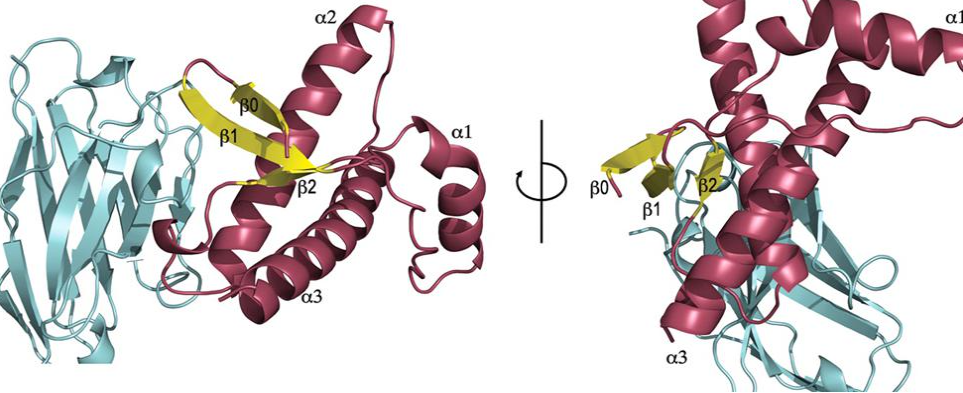

COMPOSITION FOR USE IN THE TREATMENT OF GLIOMA AND GLIOMA-INDUCED EPILEPSY

THERAPEUTIC TREATMENT AGAINST NEURODEGENERATIVE PRION DISEASES